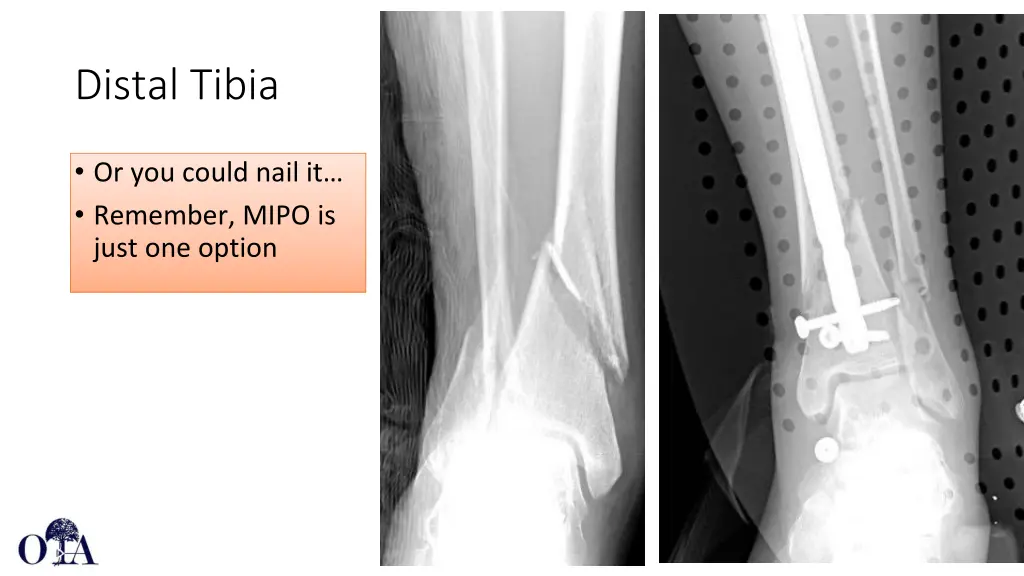

Distal Tibia Can be performed using limited open reduction (separate from incisions used for plate insertion) as soft tissues allow without increasing complication rates. In this series adding open reduction to percutaneous techniques alone decreased fluoro time and improved coronal plane alignment Kim JW, Kim HU, Oh CW, Kim JW, Park KC. A prospective randomized study on operative treatment for simple distal tibial fractures-minimally invasive plate osteosynthesis versus minimal open reduction and internal fixation. J Orthop Trauma. 2018 Jan;32(1):e19-e24. jorthotrauma.com Core Curriculum V5

Risk of wound infection is primary concern given limited soft tissue envelope over the medial ankle May lead to plate removal, debridement, need for flap coverage Core Curriculum V5

Distal Tibia Or you could nail it Remember, MIPO is just one option Core Curriculum V5